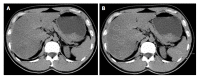

Nonalcoholic fatty liver disease (NAFLD) is one of the most common causes of chronic liver disease and is a major public health problem worldwide. It is a spectrum that includes simple steatosis, nonalcoholic steatohepatitis (NASH), fibrosis and cirrhosis. Recently, NAFLD prevalence in children and adolescents has increased too. The increasing prevalence has resulted in NASH-related chronic liver disease. Therefore, early diagnosis and treatment is quite important. Although liver biopsy is still the gold standard for diagnosis and staging of NAFLD, particularly for the diagnosis of NASH, imaging methods such as ultrasonography, computed tomography, magnetic resonance imaging with chemical shift imaging and especially magnetic resonance spectroscopy and elastography have been increasingly approved as noninvasive alternative methods. The aim of this review is to analyze the diagnostic accuracy and limitations of the imaging methods and recent developments in the diagnosis of NAFLD.